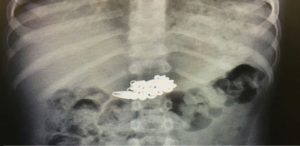

- рентген;

- пальпация брюшной полости;

Стоит отметить, что именно рентген является лучшим способом диагностики. Благодаря данной процедуре, можно увидеть камни, различные предметы и другие инородные тела, которые оказались в организме собаки.

- Рентген. Во время исследования бывают хорошо видны камни, металлические и резиновые предметы. Или же, если инородное тело не определяется, врач может заметить изменения внутренних органов, характерные для наличия инородного тела.

Глотают люди что угодно: кости, иголки, батарейки, саморезы, магнитные шарики, монеты, стоматологические съемные протезы. Все инородные тела делят на агрессивные и неагрессивные. При проглатывании агрессивных тел они должны быть удалены как можно быстрее. В то время как более-менее безопасные вещи могут выйти самостоятельно.

Всем пациентам при проглатывании костей делают рентген. По возможности кость сразу же удаляют эндоскопическим методом. В пищевод вводится трубка с камерой и инструментарием, при помощи которого извлекается инородное тело.